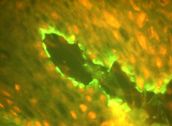

El estudio histopatológico (Nº 03-129) realizado en la Cátedra de Anatomía Patológica General y BMF de la Facultad de Odontología, informó que se trataba de una ampolla subepitelial. El epitelio se mantenía en áreas adosado a la membrana basal. El conjuntivo presentaba un infiltrado inflamatorio linfocitario, con neutrófilos, plasmocitos, abundantes mastocitos y neovasos (Fotos 8 – 10).

Foto 8 Hendidura entre epitelio de cubierta y tejido conjuntivo. Ampolla subepitelial

Foto 9 Infiltrado de linfocitos, neutrófilos y plasmocitos

Foto 10 Presencia en conjuntivo de mastocitos y neovasos. Alteración de células basales

Se concluye con un diagnóstico concordante con Penfigoide de membranas mucosas.